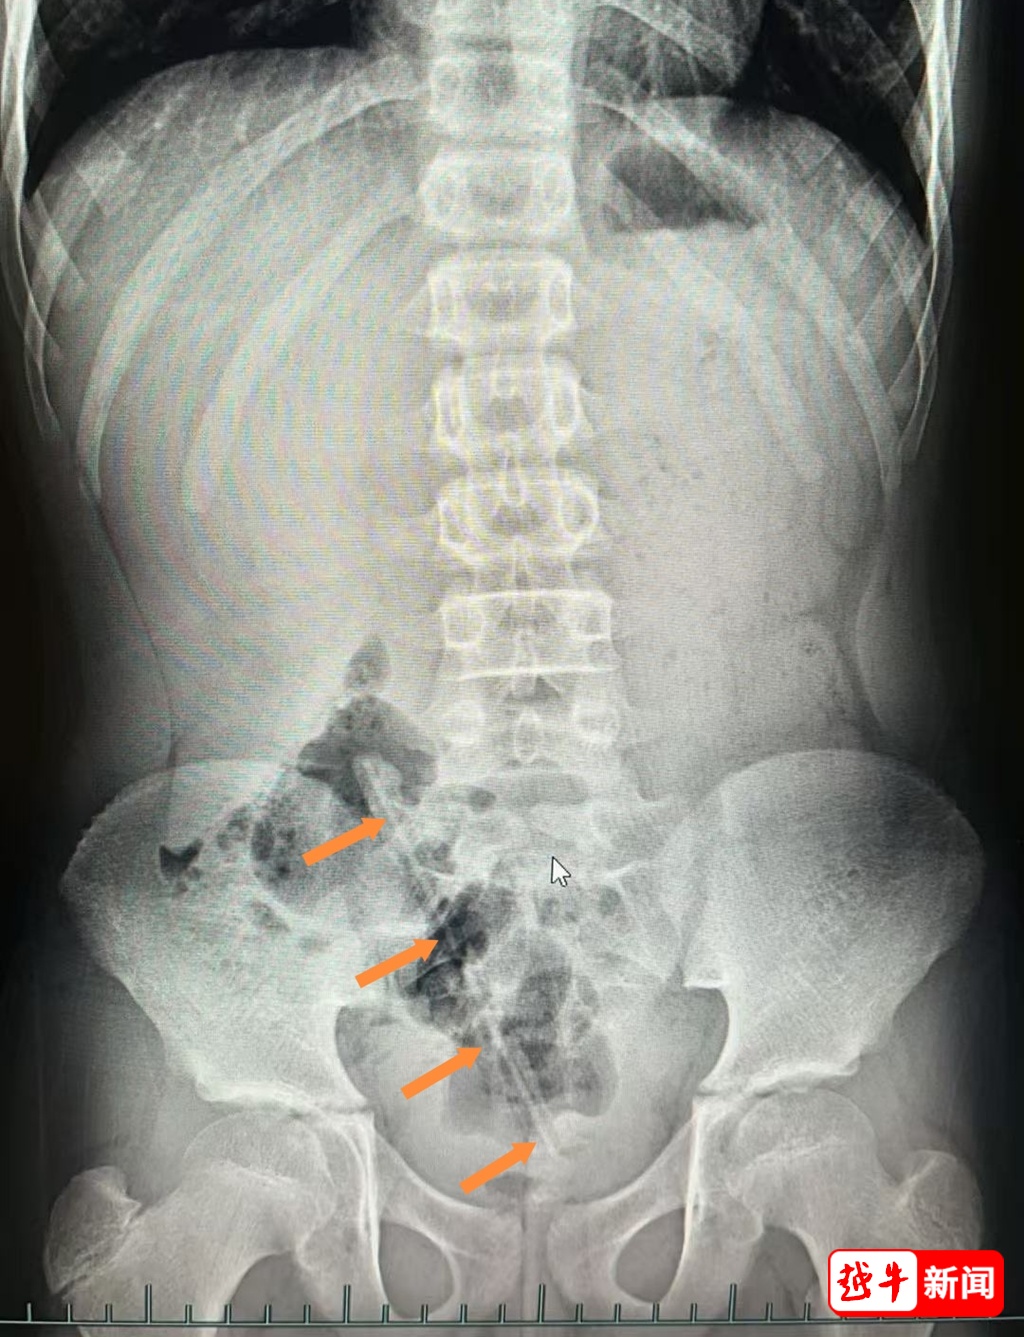

小儿外科医生屠菊英查体时在患儿右侧脐旁触及一条状物体,但肛门指检却未能探及异物。急诊腹部X线检查显示:盆腔内确有一条状异物,长度约17cm。

小木塞进肛门里的铅笔↓